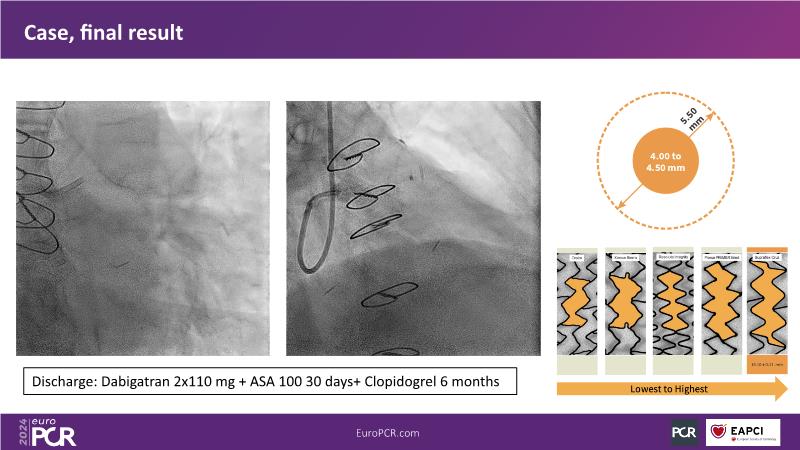

Discover the remarkable performance of Supraflex Cruz in real-world clinical settings, showcasing exceptionally low event rates and demonstrating its safety and efficacy across a spectrum of high-risk patients, including the elderly and those with high bleeding risks, and delve into the ongoing TALENT and TUDEXO II trials, designed to further elucidate the benefits of employing best PCI practices, particularly focusing on the efficacy of ultrathin struts such as Supraflex Cruz in managing complex CAD, including three-vessel disease, especially in diabetic populations.

- To learn the optimal contemporary approach in PCI, encompassing (a) patient selection, (b) physiology to decide on revascularisation, (c) intravascular imaging to optimise PCI and (d) optimal medical therapy, within the ongoing trials addressing 3-vessel disease with and without diabetes mellitus